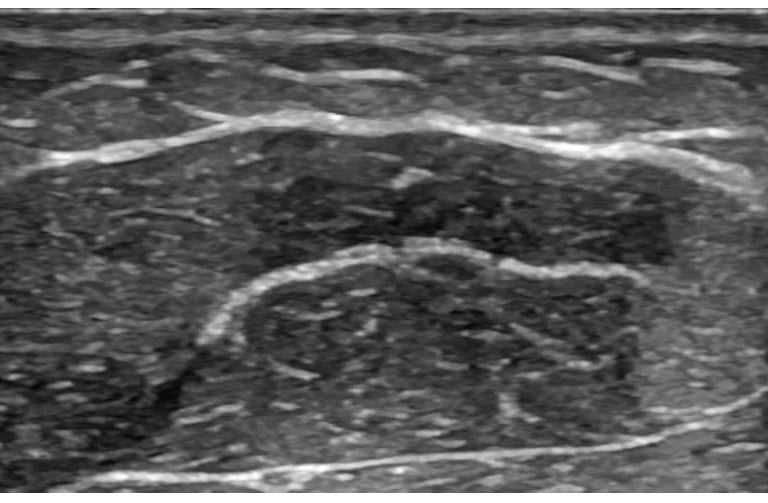

Ultrassom Intraoperatório

O ultrassom intraoperatório permite mapear estruturas e avaliar a espessura da gordura em tempo real, aumentando a precisão da lipoaspiração e a segurança do procedimento. Uma tecnologia essencial para resultados refinados e personalizados.